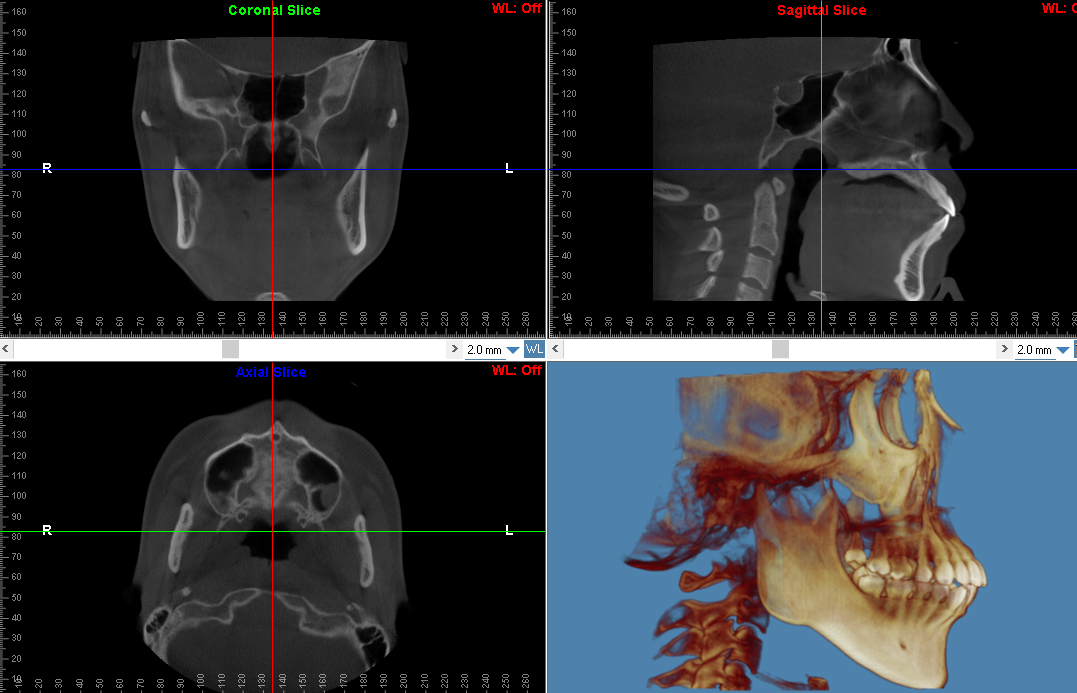

また当院では、デジタル矯正システムの良さを早い段階で理解していただくために、初回のカウンセリングで歯科用CTのスキャンデータから診断用三次元モデルを作成し、それを元にお話させていただくことも可能です。

3)CBCT撮像

・現在の口腔内の状態を詳しく説明(叢生の程度や歯並び、かみ合わせの状態)

・現在の顔貌の状態を詳しく説明(E-Line、口元の突出感、上下顎の位置)

・パノラマX線画像解析による全顎の歯根の状態、根尖病巣の有無、智歯(親知らず)の状態